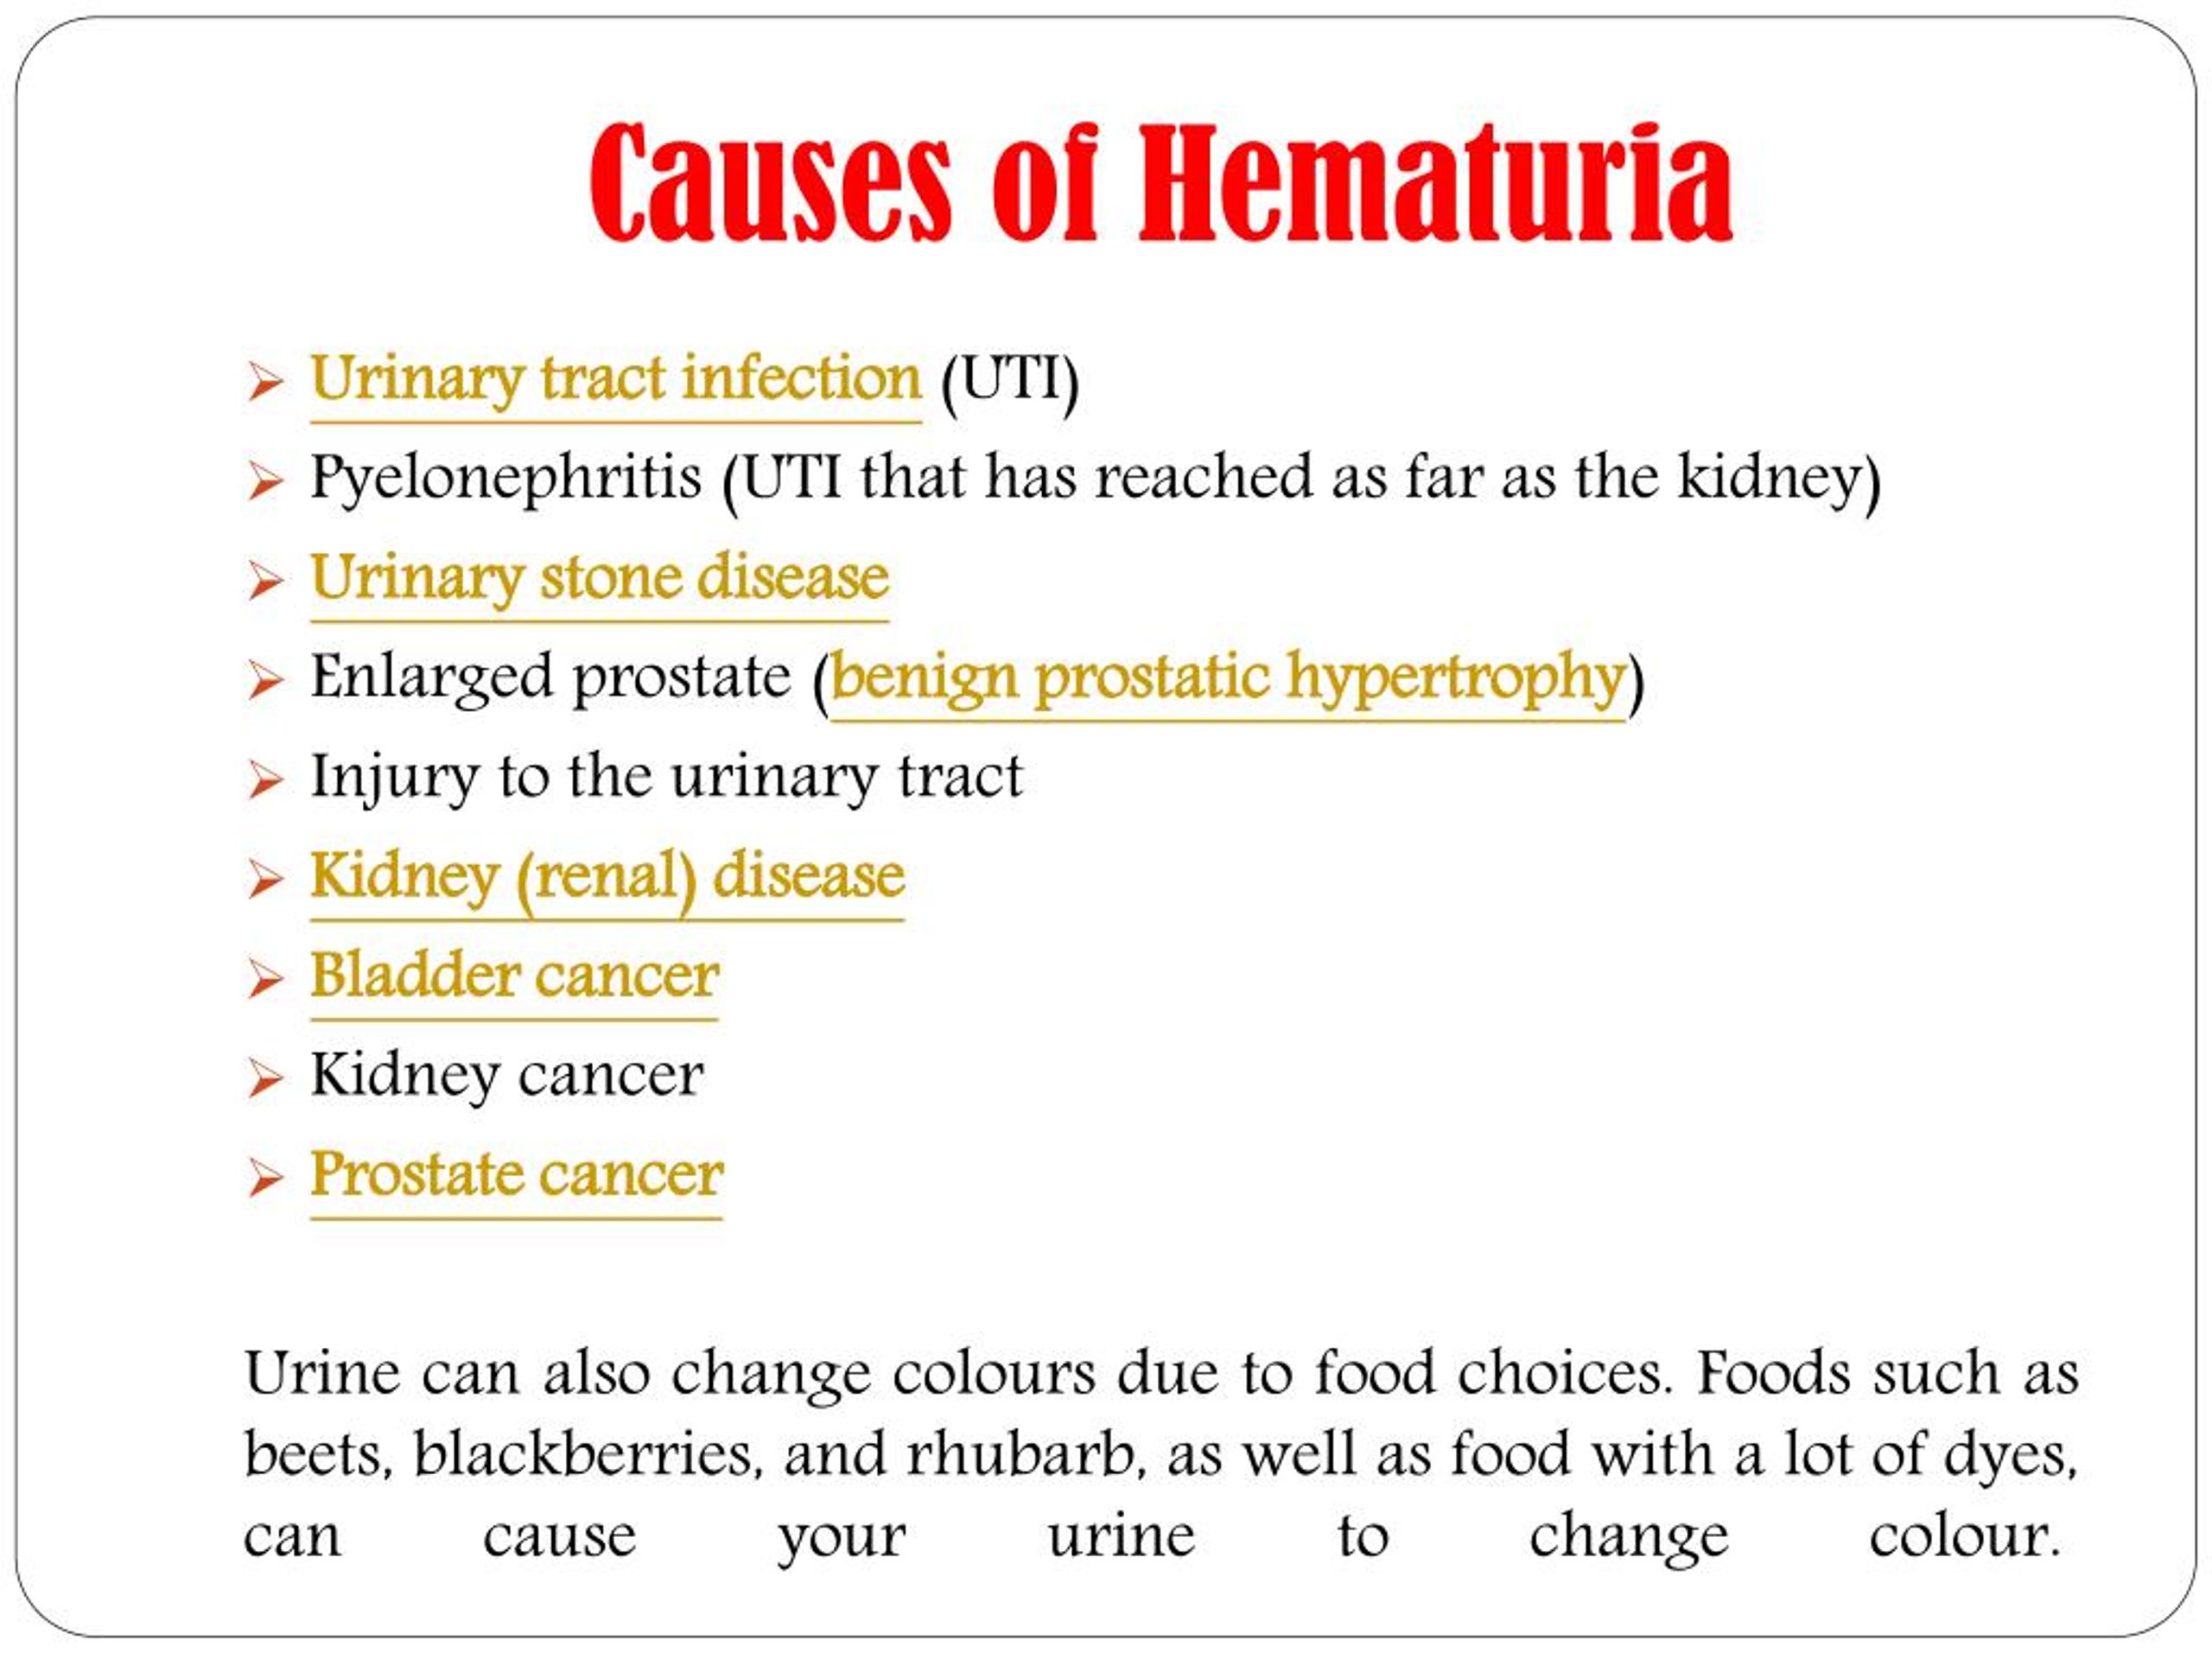

In most cases, blood in the urine (called hematuria) is the first sign of bladder cancer. There may be enough blood to change the color of the urine to orange, pink, or, less often, dark red.

Here are five warning signs to watch for:Blood in the urine (hematuria). This is the most common early symptom of bladder cancer and typically the first sign of bladder cancer that is seen. … UTI-like symptoms. … Unexplained pain. … Decreased appetite. … Postmenopausal uterine bleeding.

Symptoms to watch for that might indicate either a UTI or bladder cancer include: Hematuria (blood in your urine) Urgent need to urinate. Frequent urination. Dysuria (painful or difficult urination) Feeling the need to urinate, but nothing comes out. Needing to strain or bear down while urinating.

Blood in the urine (hematuria) Blood in the urine is the most common sign of bladder cancer and is also often the first sign noticed. This is because early bladder cancer frequently causes bleeding without pain or other symptoms.